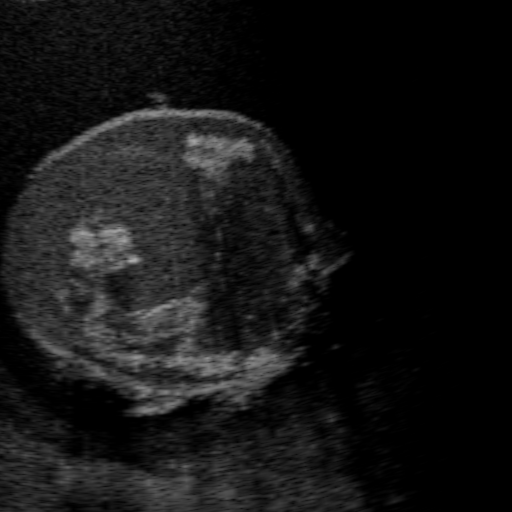

Qualitative Results. Fig. 3 shows a visual comparison of the three model variants on four examples. The baseline L2HM fails to preserve anatomical structures due to missing structural information in the input images. Resulting ambiguities in the network prediction cause artifacts such as blur in regions that feature fine details such as bones. Providing segmentation maps as additional input (L2HMS) greatly reduces such artifacts as shown in Fig. 3(c). However, L2HMS still struggles in modeling complex non-local features such as directional occlusion artifacts, note the lack of acoustic shadows in Fig. 3(c). In contrast, our final model L2HMSA is able to accurately synthesize these features and produces translations significantly closer to the target, as demonstrated in Fig. 3(d). In particular, our proposed model with segmentation and attenuation integral maps is able to recover both missing anatomical structures and directional artefacts.

(a) Input

(b) L2HM

(c) L2HMS

(d) L2HMSA

(e) Target